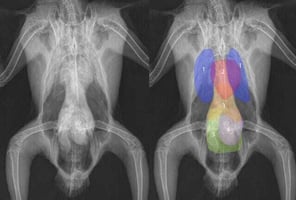

Avian anaesthesia – a guide for general practitioners

Anaesthetising avian patients is an uncommon procedure in general practice unless clinicians have a ...

17 min read